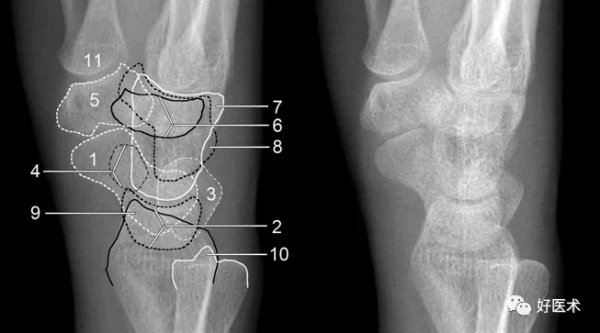

成人期腕關節正側位及舟骨蝶位片

1.舟骨 2.月骨 3.三角骨 4.豆狀骨 5.大多角骨 6.小多角骨 7.頭狀骨 8.鉤骨 9.橈骨莖突 10.尺骨莖突 11.第一掌骨基部

a. M形腕掌線 b. 腕骨弧線(Gilula線)

若顯示腕骨弧線不連續或各弧線不平行,或腕掌線M形結構消失,應高度懷疑腕關節不穩或脫位。

3.腕骨弧線

- 弧線Ⅰ為沿舟骨、月骨、三角骨近側凸面的光滑曲線。

- 弧線Ⅱ為其遠側凹面的光滑曲線。

- 弧線Ⅲ為頭狀骨和鉤骨近側的曲面。